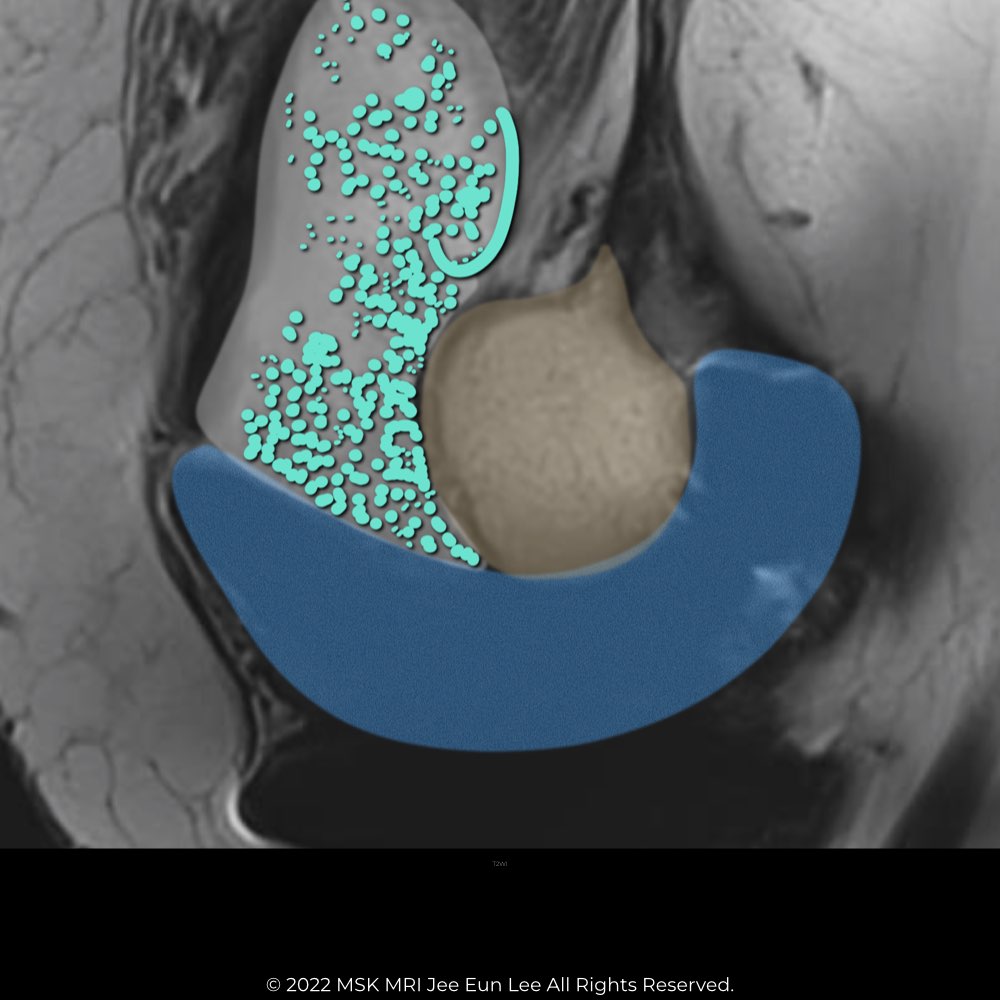

| MRI findings of Polyethylene Wear | ||

| Polyethylene wear–induced synovitis (61) (60) | Greater synovial proliferation observed on MRI corresponds with increased polyethylene wear. Frondlike synovial proliferation, thickened synovium, and intra-articular debris are seen. |